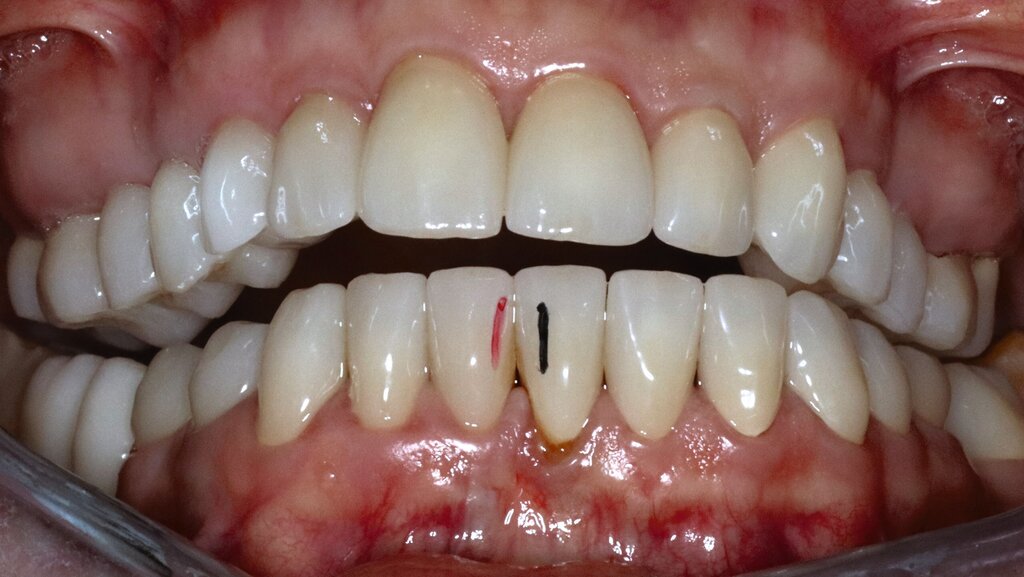

Eine 62-jährige Patientin stellte sich im Jahr 2025 in der CMD-Sprechstunde vor. Gemäß der allgemeinen Anamnese bestanden keine Vorerkrankungen. Die spezielle Anamnese zeigte den Zustand nach alio loco erfolgter prothetischer Rekonstruktion im Dezember 2024 mit festsitzendem Zahnersatz. Die Versorgung umfasste 14 Kronenrestaurationen (17–27) im Oberkiefer sowie zwölf Kronen (45–36) und zwei Implantatsuprakonstruktionen (046, 047) im Unterkiefer.

Die Patientin schilderte eine deutliche Instabilität des Zusammenbisses mit punktuellem Kontakt auf der linken und fehlenden Zahnkontakten auf der rechten Seite seit dem Tag der Insertion des Zahnersatzes. Ein annähernd stabiler Zahnkontakt sei nur durch aktiven Verschub des Unterkiefers nach rechts im Sinne eines Eingleitens in die Interkuspidation des Zahnersatzes erreichbar. Bei Provokation dieser „schiefen“ Unterkieferposition komme es jedoch aufgrund der muskulären Anstrengung nach kurzer Zeit zu Beschwerden. Die Patientin gab in diesem Zusammenhang Schmerzen und eine Grundanspannung der Kau-/Nackenmuskulatur und Kopfschmerzen an, jeweils links > rechts (Abbildung 4).

Mobilität des Unterkiefers eingeschränkt: Kieferöffnung aktiv ohne Schmerz 20 mm, aktiv mit myogenem Schmerz 32 mm, passiv 42 mm (Deflexion nach links, myogener Schmerz); unterdurchschnittliche Rechtslaterotrusion 4 mm und Linkslaterotrusion 6 mm (jeweils myogen schmerzhaft); Protrusion 4 mm (myogen schmerzhaft); Vertikaldimension unphysiologisch zu hoch (circa 2–3 mm) (Abbildungen 5 und 6).

Statische Vorkontakte 25/34 und 26/35 in geführter zentrischer Kondylenposition (entspricht dem subjektiven Erstkontakt) (Abbildungen 7 und 8) mit forcierbarem Gleiten in die maximale (Kronen)Interkuspidation circa 3 mm nach rechts (Abbildung 9).